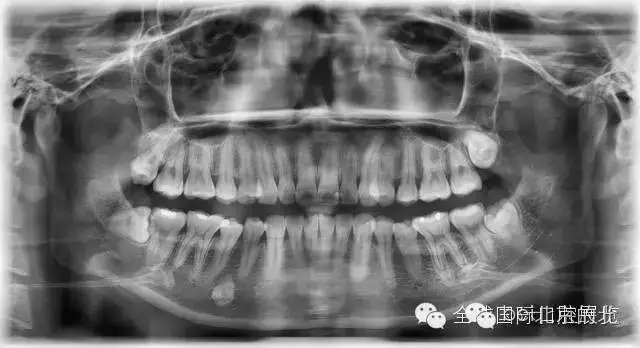

常規(guī)X-RAY全景片檢查

一個(gè)病人進(jìn)來我們不單單要關(guān)注患牙,而且要關(guān)注他們?nèi)诘难例X情況,卡瓦的跨學(xué)科病例大賽讓我更加重視了患者的全局觀,雖然患者暫時(shí)不一定會(huì)處理,但是作為我們醫(yī)生有必要告訴他們,選擇權(quán)交給患者自己,也希望和所有醫(yī)生共勉。

先看看患者別的情況: